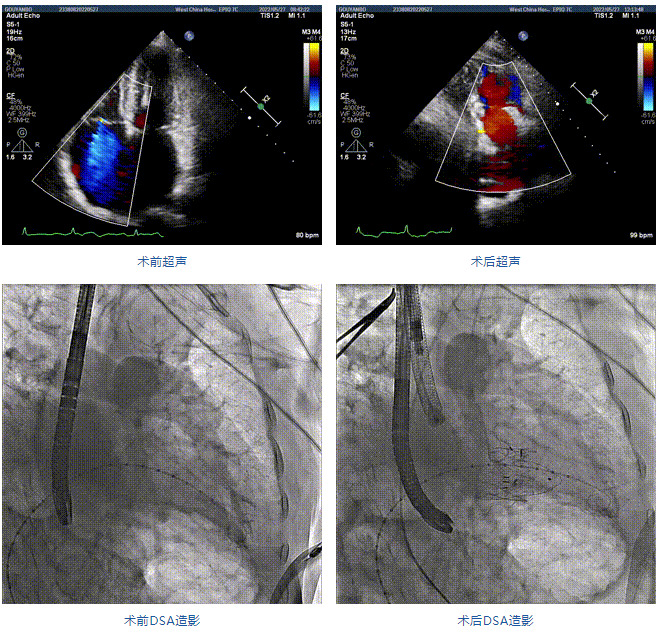

89歲男性。術(shù)前超聲報(bào)告顯示:雙房增大,左室壁肥厚,主、肺動脈增寬,三尖瓣重度反流。

團(tuán)隊(duì)前期經(jīng)過多次討論,制定了周密的手術(shù)策略和預(yù)案。由于患者已是近九旬的超高齡老人,傳統(tǒng)外科開胸手術(shù)風(fēng)險(xiǎn)極高,純介入經(jīng)血管三尖瓣替換能夠明顯減少創(chuàng)傷。術(shù)中陳茂及馮沅教授結(jié)合體表定位在造影指示下精準(zhǔn)穿刺右側(cè)頸靜脈并預(yù)置兩把血管縫合器。成功建立經(jīng)皮血管入路后在食道超聲和DSA的引導(dǎo)下順利完成人工瓣膜植入,術(shù)后超聲和造影顯示人工三尖瓣同軸性良好,瓣架固定牢靠,無反流和瓣周漏,平均跨瓣壓差降為1mmHg。術(shù)畢收緊預(yù)置的血管縫合器縫線完成止血,縫合效果滿意,在手術(shù)室即刻拔除氣管插管。